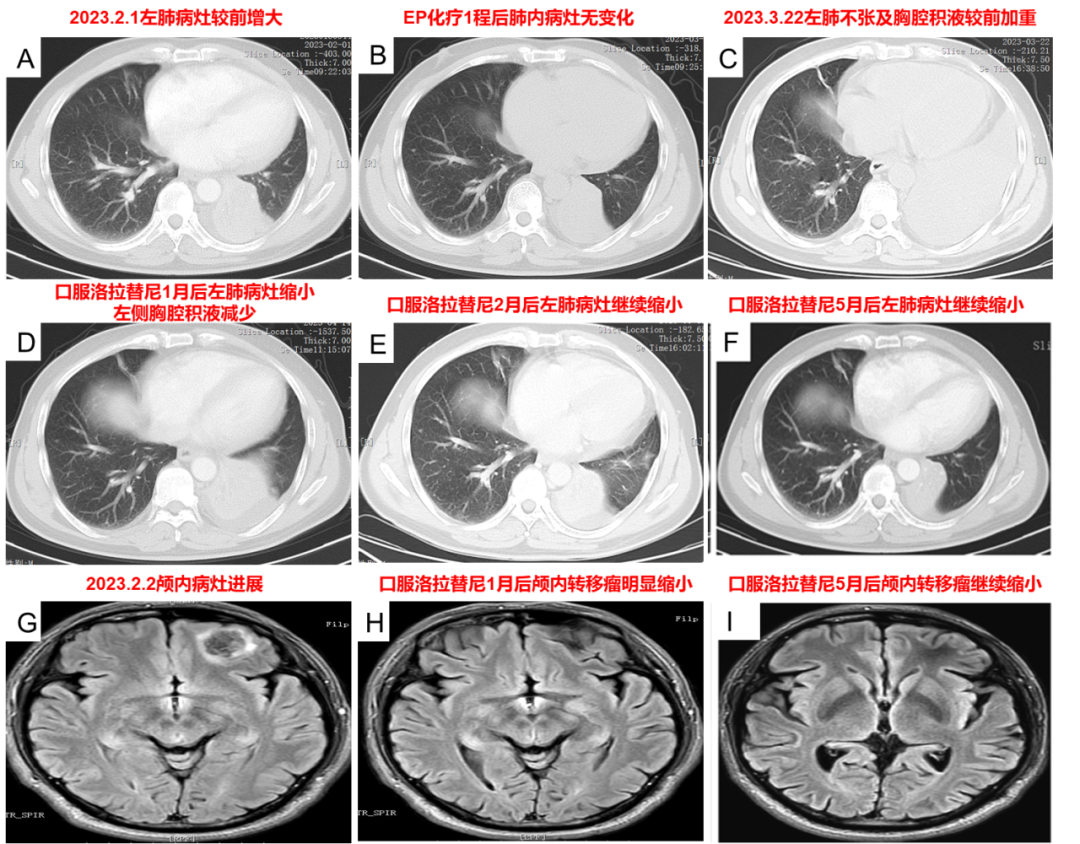

复查结果(2023-2-1):复查胸部CT示肺部病灶进展,头颅MRI示颅内病灶进展。

治疗经过(2023-3-3):2023-3-3复查左肺病灶与前相仿。2023-3-6行EP化疗第2程,左胸部出现不适感。2023-3-14开始洛拉替尼100mg QD靶向治疗,3日后出现发热、腹泻不适,发热最高体温38.9℃,腹泻每日2-3次水样便。2023-3-20就诊,考虑上呼吸道感染、消化道反应,继续洛拉替尼治疗,复查CT示左肺不张较老片加重,伴有左侧胸腔积液,对症处理后发热、腹泻改善。2023-4-14胸部CT示左肺病灶缩小、左侧胸腔积液减少,随后头颅MRI示颅内病灶缩小。2023-5-12胸部CT示左肺病灶继续缩小,伴有1级双下肢浮肿,生活质量明显改善。

图5. 洛拉替尼治疗后复查肺部及颅内病灶明显缩小